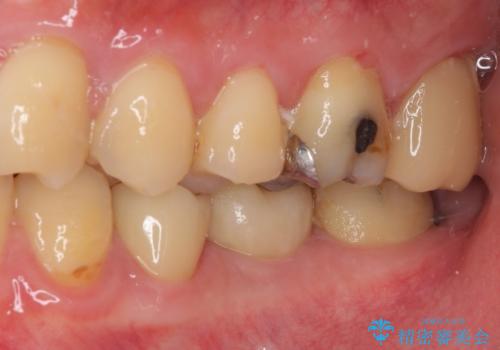

以前装着した修復物が不適であり、歯肉が腫れていましたが、仮歯を装着したことで腫れは解消されました。

歯の痛みだけでなく、歯肉の腫れも改善され、患者様には大変満足していただきました。